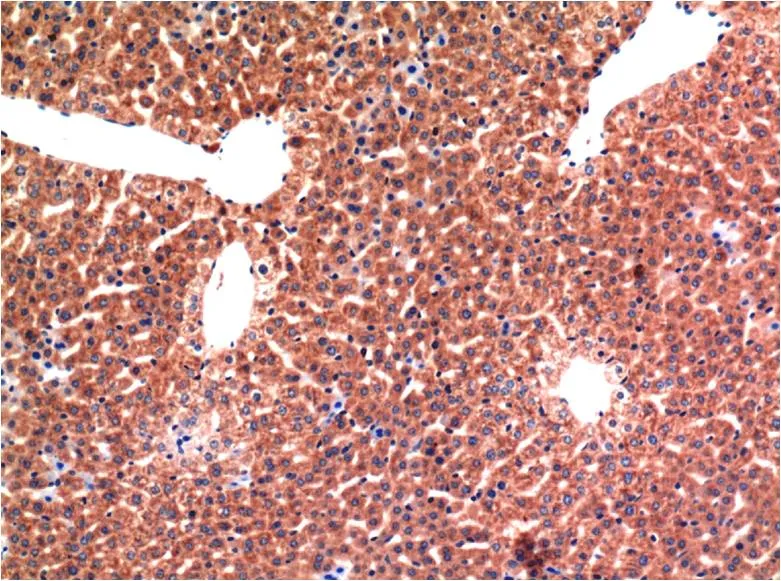

ERK1 (1D10) Mouse Monoclonal Antibody

Cat: AMM00760

Size1:50μl Price1:$150

Size2:100μl Price2:$280

Size3:500μl Price3:$1200

Size2:100μl Price2:$280

Size3:500μl Price3:$1200